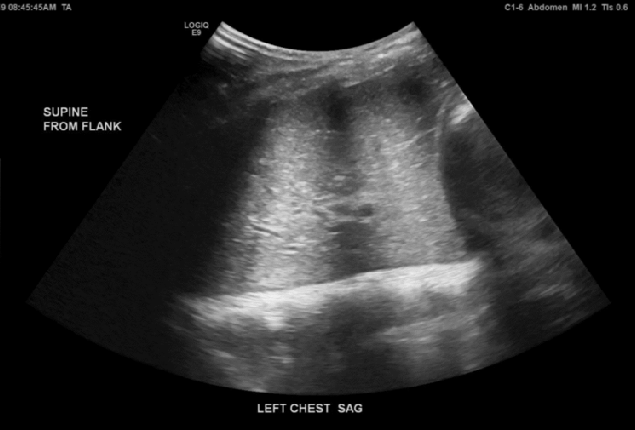

Lung Ultrasound

- Structured and systematic lung assessment

- Introduction to scoring approaches and pattern recognition

- Protocol for acute dyspnoea

- Integrating lung findings into escalation decisions